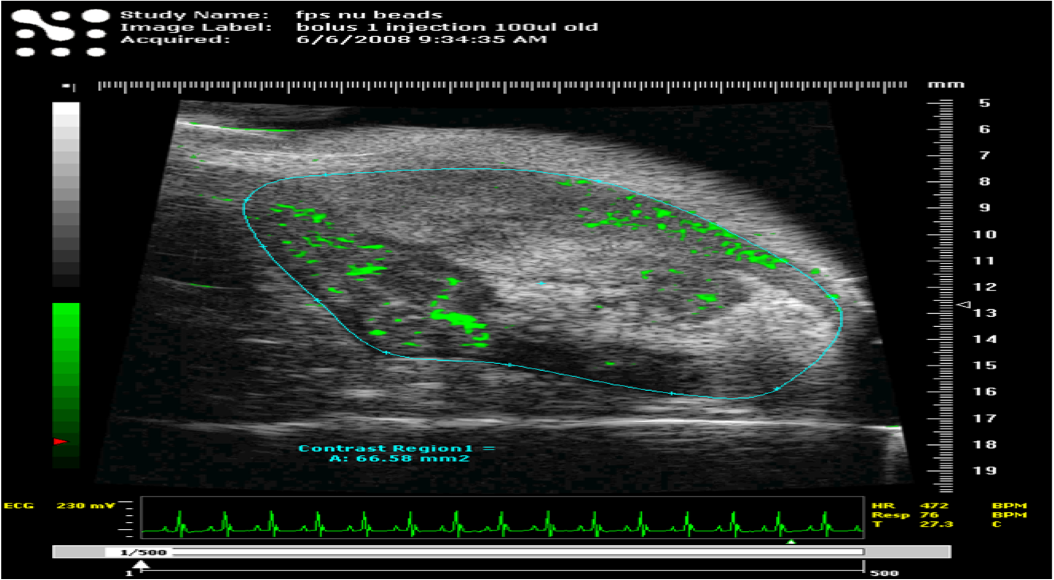

As is commonly known, ultrasound imaging works by using the interaction of sound waves with living tissue to create a 3 dimensional density image. Sounds waves are transmitted through the tissue of interest and the change in the detected echo varies with tissue density and other related factors, this allows the operator to build a line profile of tissue density, by moving the transducer over the tissue of interest and changing angles of transmission, this allows a composite 3d image of the internal structure to be produced. The Vevo system we have uses signal transducers and detection instrumentation specifically designed for small animal work, with defined heads available for both mouse and rat work.

The use of an ultrasound system helps maintain consistency in ongoing in vivo measurements and minimises the need for multiple cloned animals to be used as in compratively invasive surgical methods. It is also highly beneficial in xenograft studies as specific sites can be imaged in real time and accurately guided injections performed.